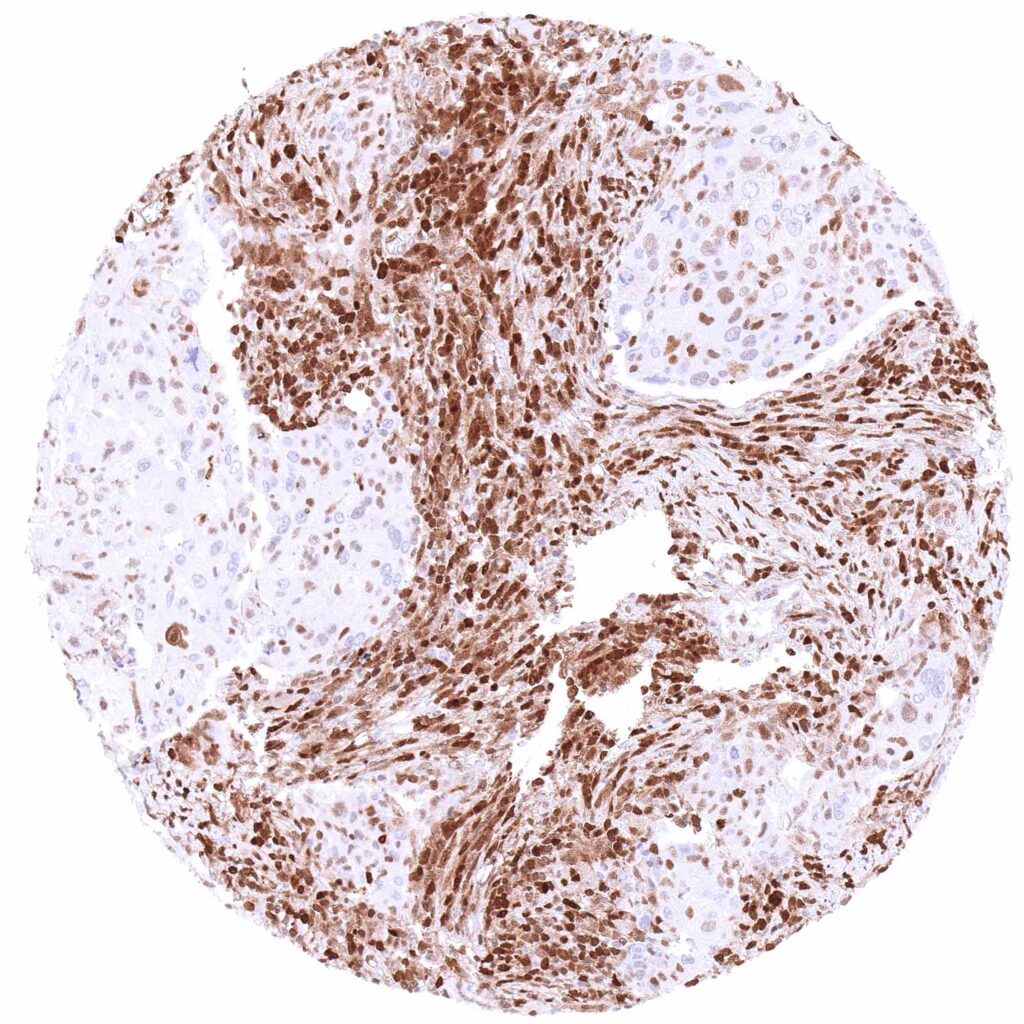

Lymph node – Diffuse large B-cell lymphoma lacking p27 staining in at least most tumor cells. Strong p27 staining of (non-neoplastic) inflammatory cells and stroma cells.